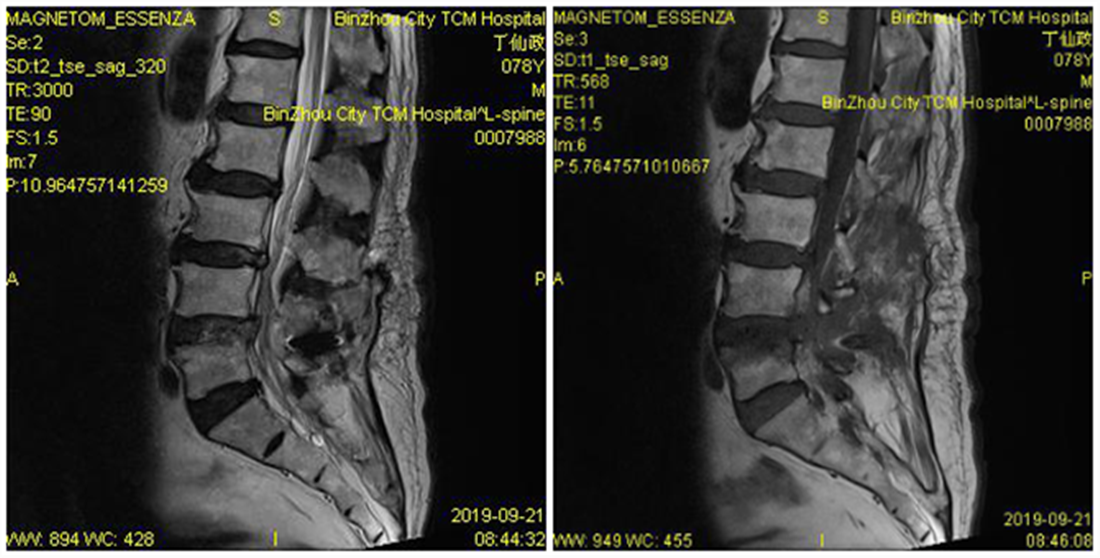

患者术后症状消失,卧床休养5天后佩戴腰围下床活动,腰骶部及右下肢疼痛消失,患者行走情况良好。经影像学检查见椎间盘突出组织摘除完全,硬膜囊及脊神经根减压充分,同时棘突间动态固定系统(COFLEX)位置良好,同时椎间隙高度良好。

术后MRI